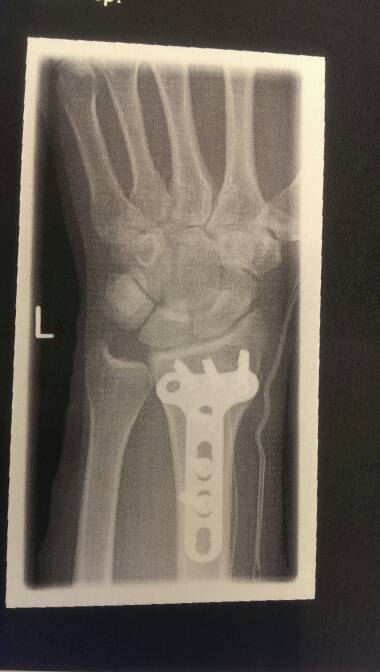

Aber dies ist wohl nicht mein bike jahr. Erst hat mich ein sturz im April für fast 10 wochen außer gefecht gesetzt und jetzt kommt noch ein operierter schleimbeute hinzu. Was auch nochmal 4-6 wochen genesung veranschlagt, damit ist mein Alp-X auch ins wasser gefallen